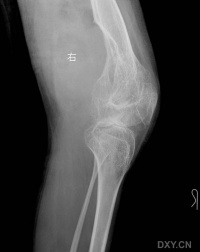

血友病性关节炎

血友病的出血常累及活动较多和承受重力的膝、躁、肘和髓关节,其中以膝关节最为常见。

中期由于酶的作用使滑膜纤维化透明软骨分解,引起慢性滑膜炎软骨退变和关节表面侵蚀。滑膜增殖引起软骨边缘和软骨下骨侵蚀。软骨的退变与破坏导致关节间隙变窄。关节运动受限可引起废用性骨质疏松

晚期出现软骨下硬化和囊变及关节周围软组织萎缩

生长发育,本病使骨髓充血、骨髓内出血以及关节内反复出血,致骨髓变形,骨筋或干髓端增大变方、股骨裸间窝增宽加深。